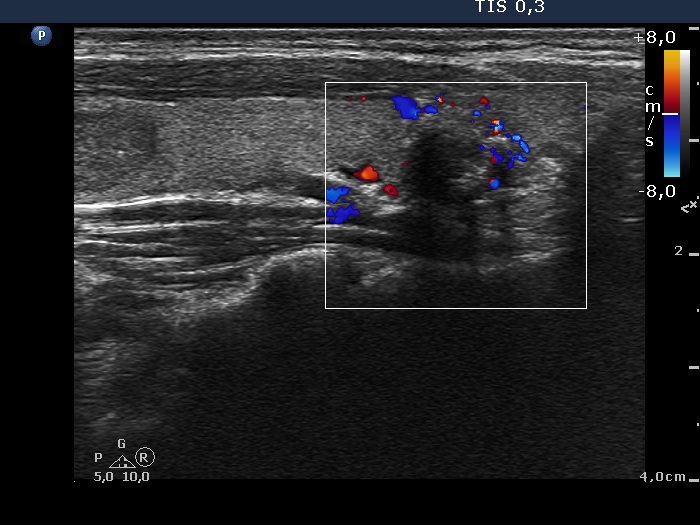

Ultrasonography. The thyroid was echonormal and contained multiple nodules including a hypoechogenic one in the lower pole of the right lobe presenting coarse calcifications. The nodule in the lower part of the left lobe was also noteworthy.

Comment. Although tht cytological pattern of the right lesion corresponds to a follicular tumor if we consider the ultrasound presentation than the risk of a follicular neoplasia is very low: the lesion exhibited neither halo sign nor perinodular bloodf flow. It means that there were not present any signs of a capsule. In such cases the risk of a follicular tumor is less than 5%.